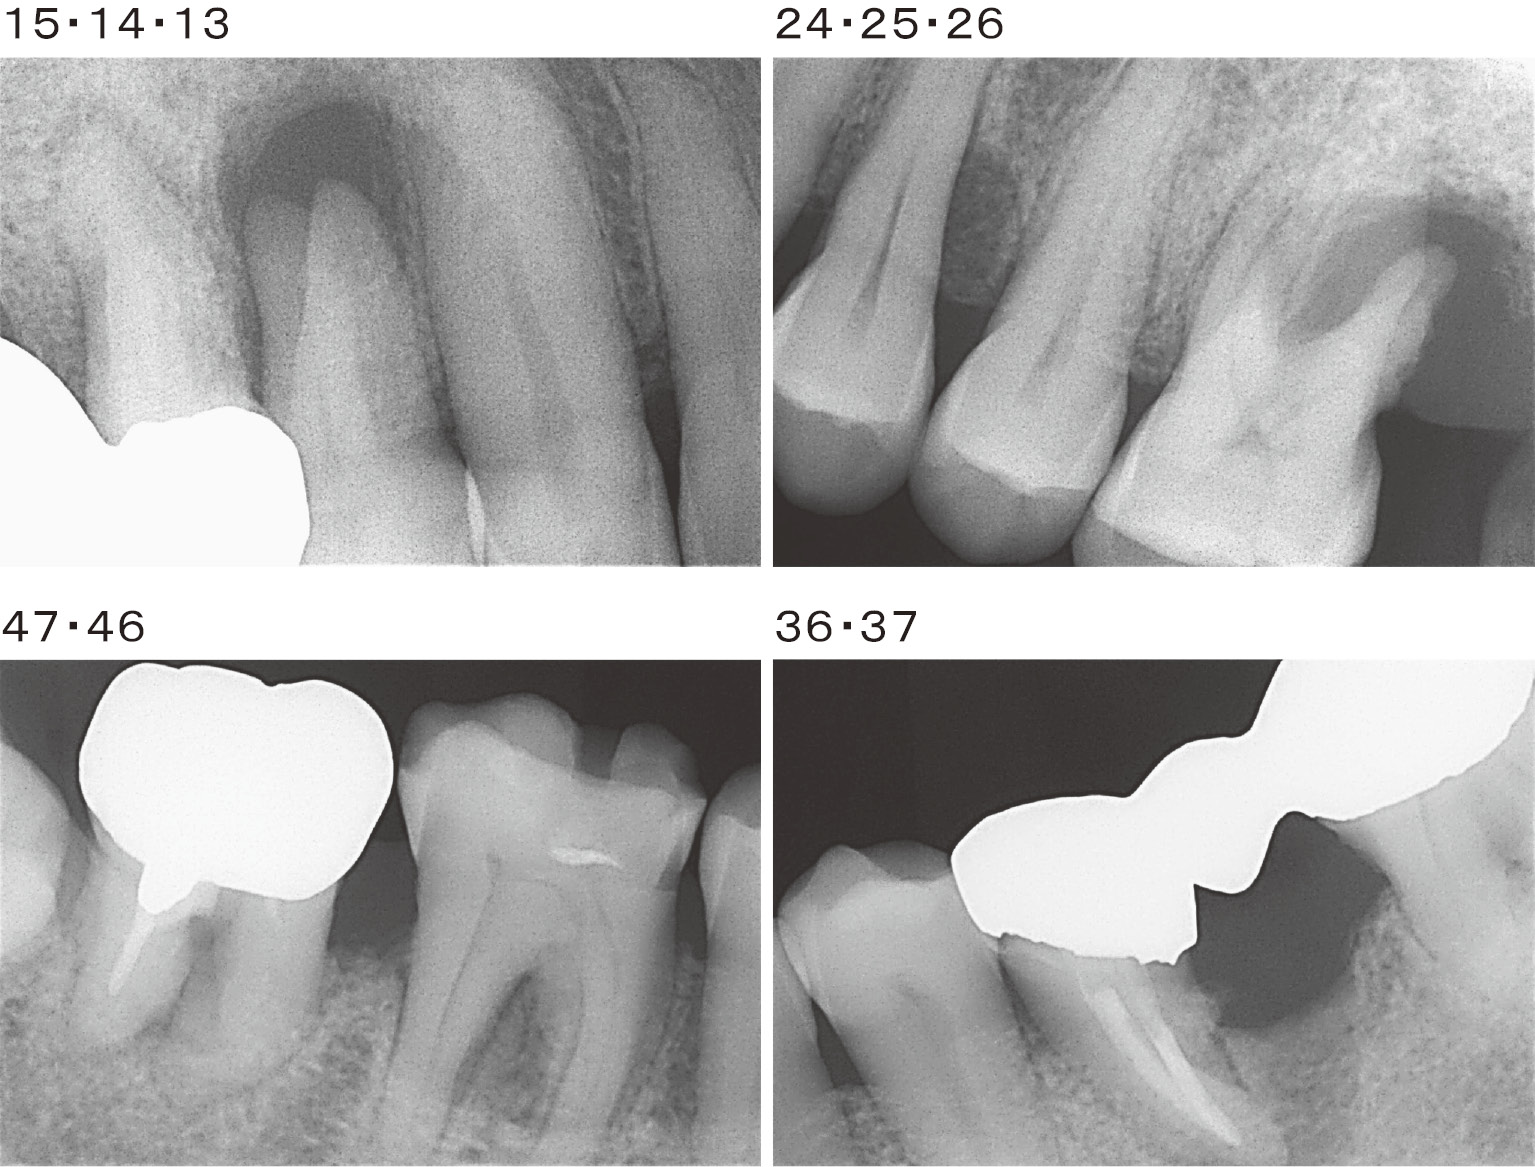

また,エックス線所見では14,24,25,36,45に垂直性骨吸収像と26,37,46,47に根分岐部病変が認められた。36は遠心根が分割抜去18)されていた(図3-1,3-2)。

初診時デンタルエックス線写真(2011年4月)

さらに,歯周組織再生療法を行った部位のデンタルエックス線所見で14近遠心部,24遠心部,36遠心部で垂直性骨吸収像の改善と46,47の根分岐部に硬組織の造成が認められた(図7)。

歯周組織再生療法を行った部位のデンタルエックス線写真(2012年7月)

パノラマエックス線写真(図10)では初診時に比べ全顎にわたり歯槽硬線の明瞭化が認められた。また,歯周組織再生療法を行った部位のデンタルエックス線写真の初診時とSPT時の比較(図11)では,15,14,13垂直性骨吸収像の改善,24,25,26垂直性骨吸収像の改善と骨梁構造の緻密化,36近遠心部の硬組織の造成と歯槽硬線の明瞭化,37,46,47根分岐部に硬組織の造成が認められた。

歯周組織再生療法を行った部位のデンタルエックス線写真~初診時(上段)とSPT時(下段)の比較